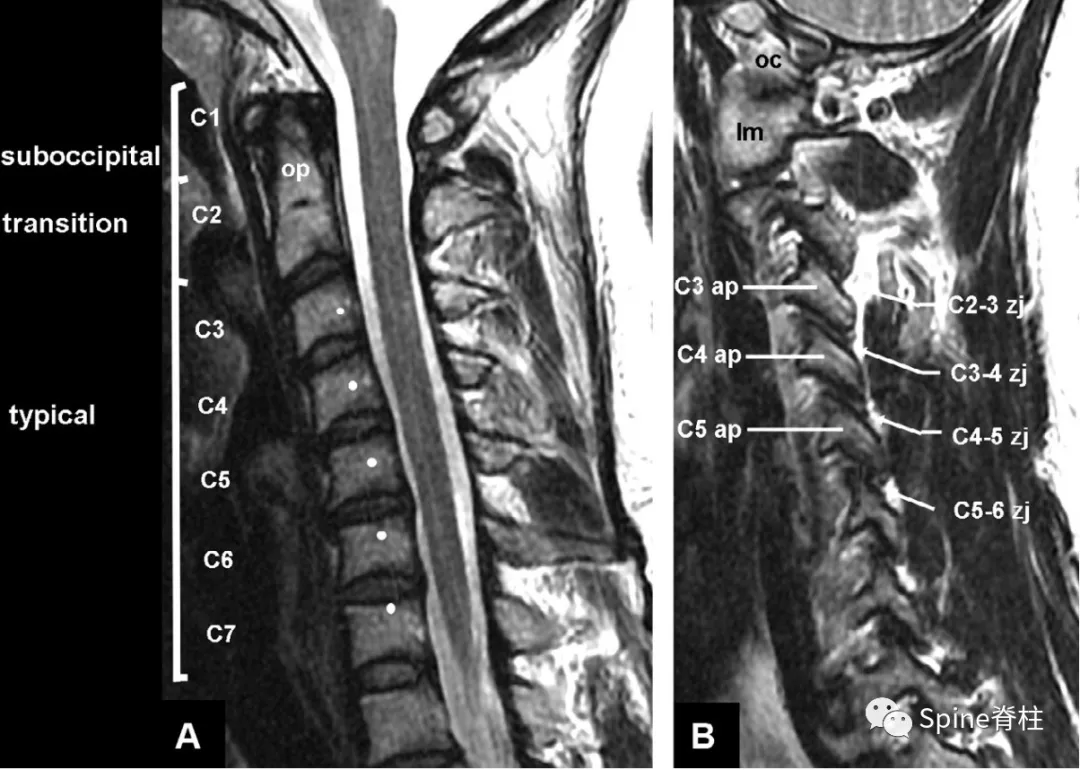

颈椎典型锥体c3c6

节段型:病灶不连续,位于c2~c6椎体后方,t2wi上呈混杂信号,整体以低

冠状面,在钩突(u)之间,c6椎体呈凹面向上,与c5的凸面向下形成椎间关节